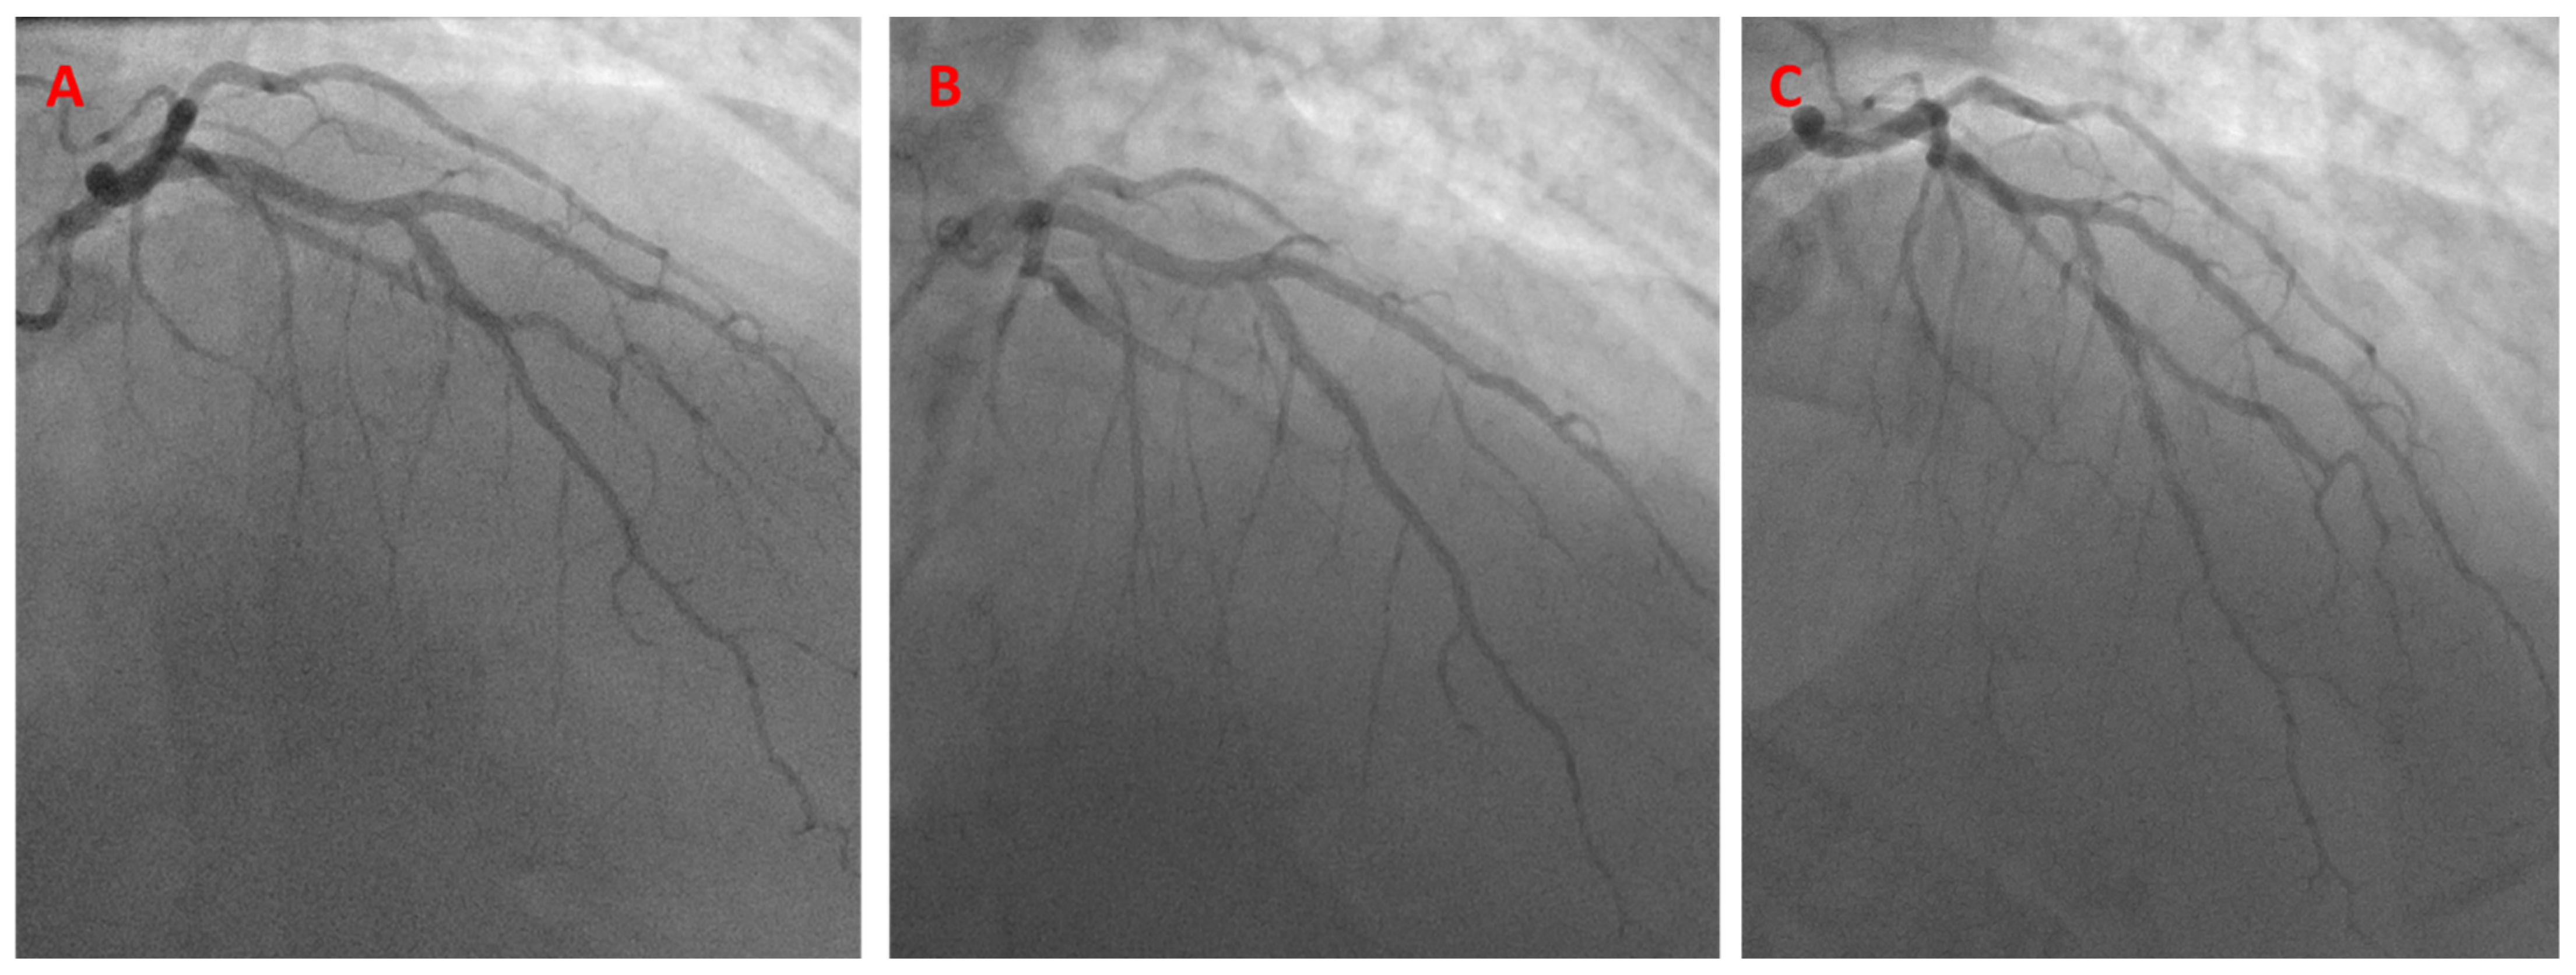

A 41-year-old man with hypertension, hyperlipidemia, type II diabetes mellitus, active smoking, a history of stroke, chronic obstructive lung disease, and morbid obesity presented with unstable angina. A diagnostic coronary angiogram showed severe 70–80% stenosis in the mid-LAD, right at the diagonal branch takeoff point. PCI was then performed using an 8 French JCL-4 guide catheter. The kissing BS technique was performed at the LAD/diagonal bifurcation, using a 3.0 × 18 mm Cypher stent in the mid-LAD and a 3.0 × 15 balloon in the diagonal branch, with successful angiographic results (Figure 8).

Figure 8.

Initial angiogram showing mid-LAD disease (A). The K-BS intervention, using a balloon in the diagonal branch and a stent in the LAD (B). Final angiographic result (C).